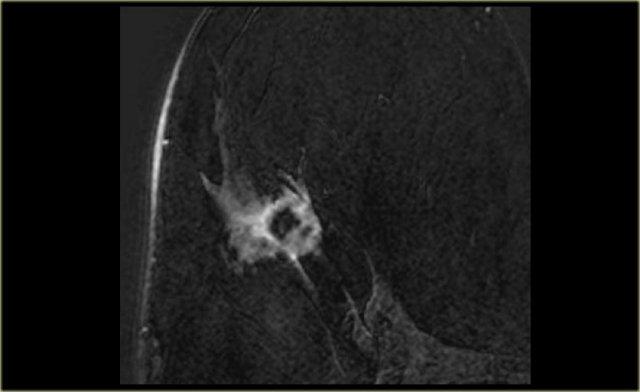

Bờ tua gai thường là đặc điểm của các tổn thương vú ác tính và sẹo hình tia.

Nếu một khối có bờ tua gai, khả năng ác tính là 80%.

Hình ảnh ngoài cùng bên trái cho thấy một khối có bờ tua gai, tức là khả năng ác tính 80%.

Bên cạnh đó là mẫu bệnh phẩm đại thể tương ứng.

Có thể thấy các tua gai xâm lấn vào mô xung quanh trong cả hai hình.

Tương tự như trên nhũ ảnh, tổn thương này có khả năng ác tính cao và sẽ được phân loại BIRADS 5.